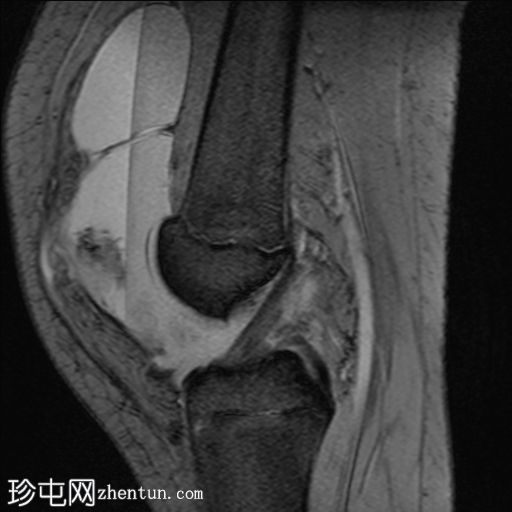

矢状位

PD脂肪抑制序列

关节内大量积血,可见血细胞比容增高征。股骨外侧髁前部及髌骨内侧可见挫伤性微骨折。髌骨内侧支持带及髌股内侧韧带水肿增厚。髌骨内侧关节面下关节软骨浸润,提示I期骨软骨损伤。

髌骨外侧隐窝可见游离体,其信号强度与关节软骨一致,提示髌骨关节软骨外剥离损伤。股骨滑车和股骨关节软骨正常。

胫骨近端和腓骨骨骺以及股骨远端延伸至干骺端的骨骺周围可见局灶性骨髓水肿。这些提示存在局灶性骨骺周围水肿区。

十字韧带和侧副韧带正常。半月板正常。股四头肌腱和髌腱正常。

该病例具有短暂性髌骨外侧脱位复位损伤的特征性表现,包括预期的骨挫伤模式、内侧髌骨支持带/内侧髌股韧带损伤、髌骨骨软骨损伤以及髌骨软骨游离体。